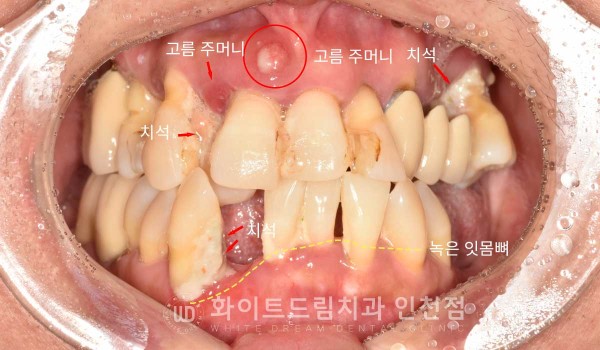

✔ 치주 질환으로 인한 잇몸뼈 손실

치주염이 심한 경우, 잇몸뼈가 녹아 잇몸의 높이가 낮아집니다.

✔ 뼈이식 한계

수직적으로 잇몸뼈가 많이 소실되면 뼈이식만으로 완전한 회복이 어렵습니다.